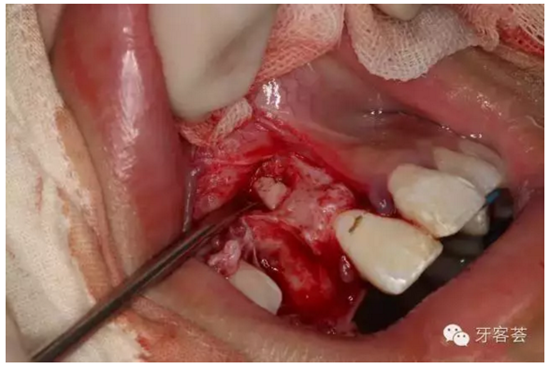

圖11:根據(jù)根尖片準(zhǔn)確定點(diǎn)根尖區(qū)位置、并用超聲骨刀去骨。

圖12:去骨、暴露11根尖區(qū).

圖13:繼續(xù)用骨刀修整根尖區(qū)四周骨壁。

圖14:超聲骨刀去骨約5mm范圍,暴露折斷的根尖1/3.

圖15:微創(chuàng)牙挺取出根尖1/3斷根。

圖16:超聲骨刀清理骨腔周?chē)M織